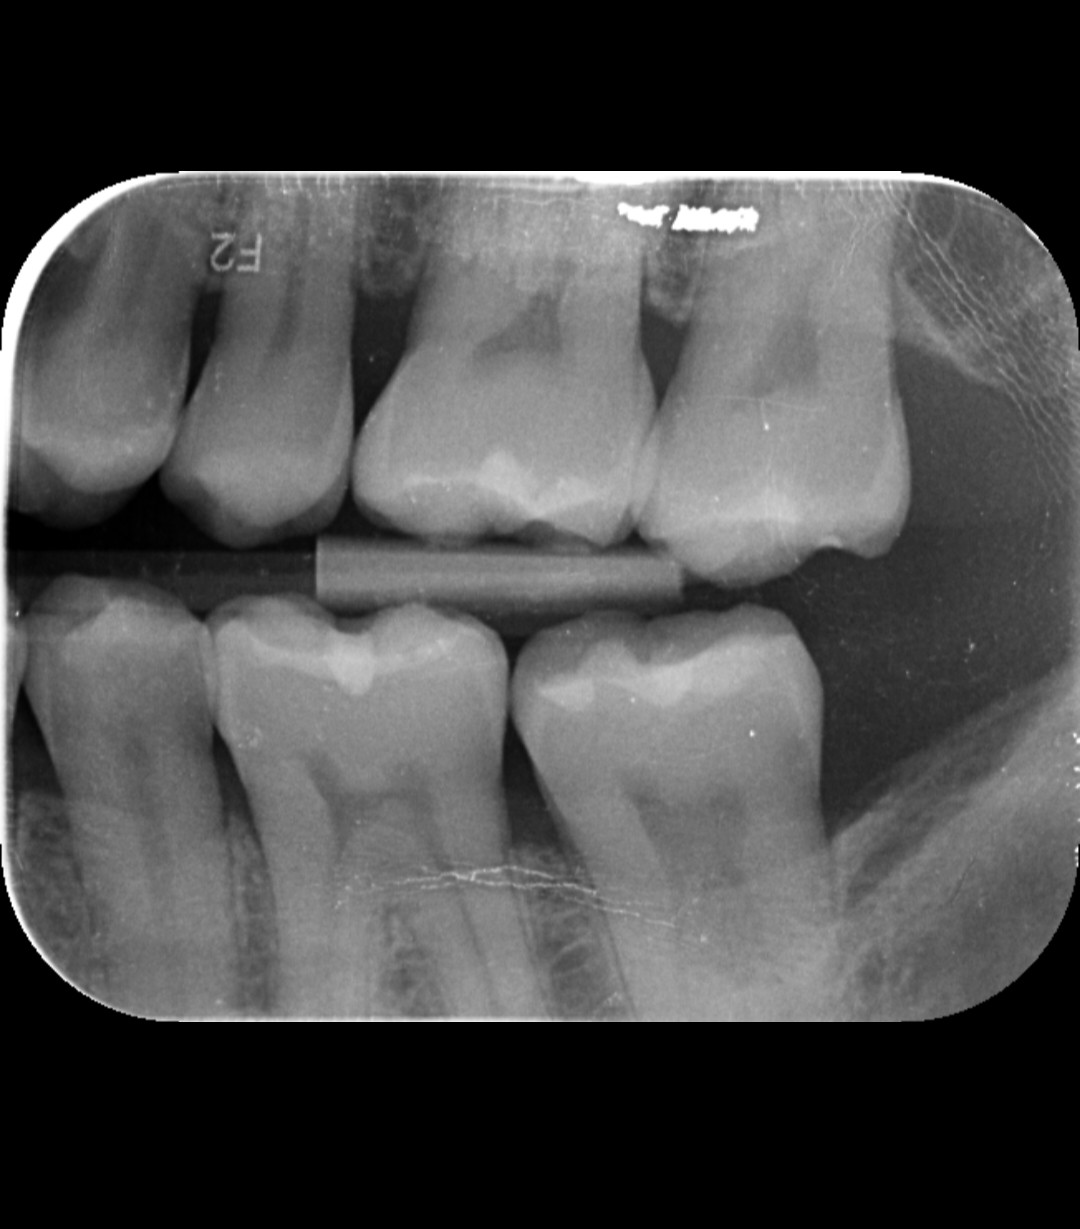

Ich habe wegen Umzugs den Zahnarzt gewechselt und seit vielen Jahren wieder mal ein Röntgen machen lassen. Ich hatte noch nie Karies. Am Schneidezahn vor dem Backenzahn unten links soll laut Zahnärztin Karies sein. Ich sehe nichts. Können Sie etwas erkennen? Vielen Dank für die Hilfe! MfG